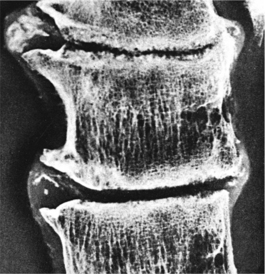

OA is classified based on clinical information and radiologic evidence. The radiographic classification used most often is the 0 to 4 grading system proposed by Kellgren and Lawrence (Box 27-7).242 Grade 4 changes include large osteophytes, severe joint space narrowing, bony sclerosis, and bone exposure (Fig. 27-5).

Figure 27-5 Osteoarthritis of the knee. Proliferative marginal osteophytes (larger arrows), narrowing of the medial weight-bearing joint space, and eburnation (exposure of the subchondral bone, surface becomes smooth and polished as it wears down) (smaller arrows). (From Noble J: Textbook of primary care medicine, ed 3, St Louis, 2001, Mosby.)